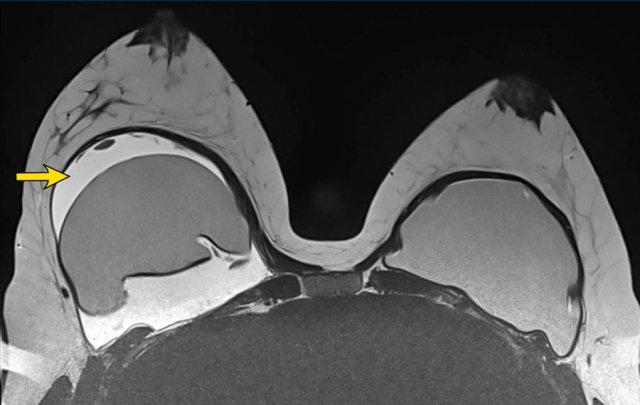

Trên hình CT cắt ngang này, có hình ảnh dày bao xơ kèm vôi hóa bao xơ nặng nề.

Ở bên phải, ngoài ra còn thấy hình ảnh nội dung không đồng nhất và một số đường thẳng dạng tuyến, gợi ý vỡ túi trong bao xơ.